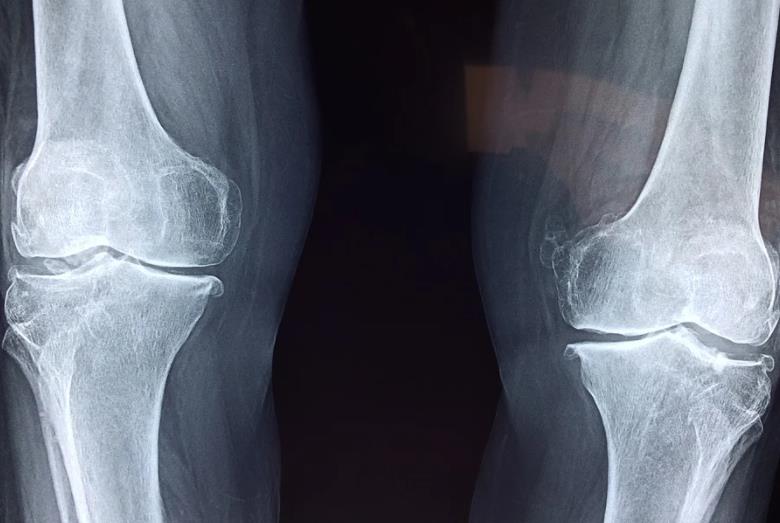

넷, 골다공증, 관절 통증 완화

MSM 관련 연구결과들을 보면 관절염이나 뻣뻣함, 관절 통증, 허리와 무릎에 문제가 있는 사람들이 MSM을 섭취했을 때 증상이 호전된 데이터들이 많습니다. 관절의 염증은 줄이고, 콜라겐 생성을 도움으로서 유연성을 높이고, 통증을 가라앉히는데 도움을 줄 수 있습니다.